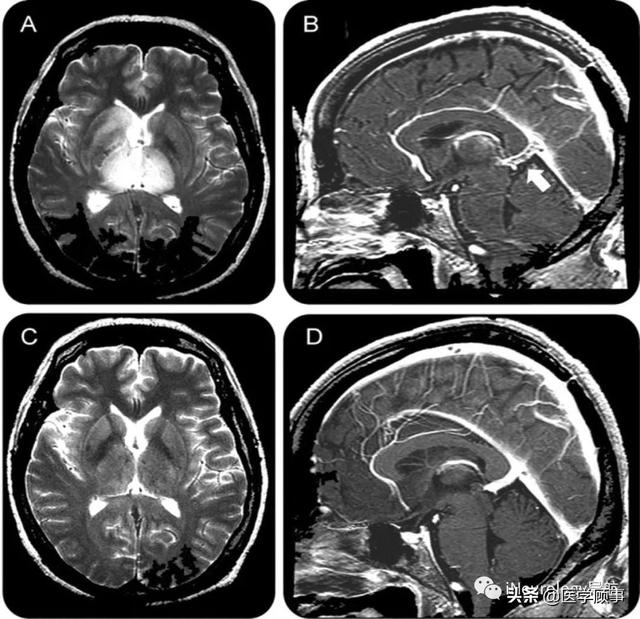

3 galen静脉动脉瘤样畸形磁共振成像 a.

neurology病例:galen静脉血栓形成的可逆性双侧丘脑病变